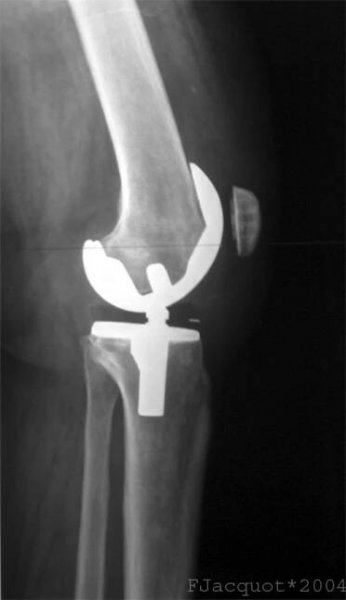

Obr. 4a: RTG obraz náhrady kolenního kloubu